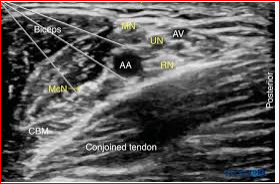

Ultrasound-guided brachial plexus blocks in pediatric anesthesia: non-systematic review<br /><br />Majid Fakhir alhamaidah*1,2, Hussein Ali Hussein 2,3, Hussein alkhfaji 2,4, Sami Raheem Hasan2, Mohammed AbdulZahra and Sasaa5Ali B. Roomi6 <br /> AL-Rifaei General Hospital, Iraq. <br />2 Department of Anesthesia, College of Health and Medical Technology, Al-Ayen University, Iraq<br />3 Nasiriya heart center<br />4 Bent AL Huda hospital, Iraq.<br />5 AL-Mustaqbal university college, department of anesthesia Babel, Iraq <br />6 College of Health and Medical Technology, Al-Ayen University, Iraq. <br />Abstract <br />Background: The ultrasound guidance for regional anesthesia has gate a widespread as a recent technique to identify, visualize, and monitoring targeted nerves, needle insertion, local anesthetic injection and distribution, catheters and adjacent anatomical structures, and helps to avoid complications such as inadvertent intravascular or intrafascicular injection in comparison to other traditional techniques.<br />Purpose of review: To show and explain if any superiority has added to brachial plexus approaches with this sonography guidance for the pediatric population over other traditional techniques in terms of increasing the success rate or reducing the complications.<br />Methods: Three authors independently searched the literature using MEDLINE and EMBASE bibliographic databases, Cochrane Central Register of Controlled Trials (CENTRAL), and manually in either the title or abstract, we also searched Google Scholar, Web of Science and reviewed the references of included trials for potentially relevant trials.<br />Results: Reviewed literature suggests that ultrasound-guided peripheral blocks reduce block performance time in comparison with nerve stimulation, increase the success rate, reduced intended LA agent, and increase the quality of the block (as measured by analgesic consumption, block duration, and pain scores). <br />Conclusion: The introduction of ultrasound imaging improved the safety profile, reduced performance time, and advanced the upper limbs block approach.<br /><br />Keywords: Ultrasound, regional block, brachial plexus, upper limb, upper extremities, pediatric anesthesia. <br /><br />Introduction <br /> Ultrasonography represents a real-time nerve visualization and drug deposition around it, other internal structures including vessels, needle, and catheter became possible to be visualized by this technique. However, its application needs some basic skills (1). Pediatric patients are unlike adults in their anatomical and physiological features, and the landmark technique is not reliable in all patients due to the variability in the age and size (2). With the advancement in sonographic technology, the success rate of blocks has increased and the recommended dose gate less than with other traditional methods for pediatric regional blocks for upper extremities with the assistance of high-frequency transducers (2). There is a tight area around nerves and plexuses in the pediatric group, which is unique to this population that gives better block under ultrasound probe. The pediatric group is not a homogenous population, but they range from neonate to an adolescent and follow to that the depth of nerves and plexuses varies with the age ranging (2).<br />Recently searched published articles showed significant advantages in the field of pediatric anesthesia of the upper limbs, involve the faster sensory and motor blockade and extended duration of sensory blockade compared with using nerve stimulation alone in children (3). Ultrasound-guided upper-extremity peripheral nerve blocks (e.g. axillary, infraclavicular, interscalene, supraclavicular) in children can be performed successfully and safely with a recommended LA dose(4). In addition to reducing the muscle contraction pain that is associated with nerve stimulation with the feasibility and efficiency of ambulatory peripheral nerve catheters in pediatrics (5). <br />Methods<br /> In this review, we searched the current literature available on MEDLINE, EMBASE, and Cochrane Evidence-Based Medicine Reviews. Furthermore, citation reviews and manual search of new journals related to pediatric anesthesia or surgery were done. We included all parallel randomized controlled trials that evaluated the effect of ultrasound guidance to perform a regional blockade technique in children. Comparative studies, question studies, case series, systematic and non-systematic reviews including one or more approaches for brachial plexus blocks were searched. Searching was limited to English language and full-text articles. Four authors read all selected articles independently and a consensus was achieved. The keywords used, alone and in combination were: ultrasound, regional block, regional anesthesia, pediatric anesthesia. A further search of older literature was deemed unsuitable, and ultrasound guidance has only become a usable modality in the last few years. The goal was to review studies about regional anesthesia in pediatrics with peripheral nerve block techniques by comparing ultrasound-guided peripheral nerve block of the upper extremities either alone or by combination with at least one other technique of nerve identification such as; anatomical landmark, paresthesia, or using of a nerve stimulator. <br /><br />Technical Consideration for Pediatrics<br /> Since body water percentage is higher with pediatrics, the identification of body structures like neurons, plexuses is better than adults under the ultrasound guidance, furthermore, bony structures have less ossification making a good quality image. Nerves, plexuses, and other structures in infants and young children are located superficially and could easy visualized by the ultrasound probe. A proper instrument to patient size and age should be available for that. Suitable needle size is needed to avoid nerve injury, and good quality transducer to gate suitable resolution for superficial structures should be prepared (2).<br />Brachial plexus block<br /> The innervation of upper extremities is derived from the brachial plexus which is composed of the union of the cervical roots from C1 to C8 and part from the T1. The main anatomical differences between pediatrics and adult populations, which increase the risk of regional lock during needle insertion with perisubclavian approaches, that the superior part of the lung and apical pleura enter the neck, above the superior thoracic aperture making the risk of plural invasion bigger than with the adults. New ultrasound technology reduced these complications by offering direct and real-time visualization of the needle and any adjacent structures with supraclavicular and infraclavicular approaches.<br /> Brachial plexus block may be achieved at several sites, the appropriateness of each block is determined by the location of the surgery, the ability to properly position the patient, and assessment of pre-existing patient morbidities. The advancement in ultrasound application techniques gave the confidence for aesthesia practitioners to approach the more proximal brachial plexus even in infants and young children, instead of the axillary site which has previously been a preferred location of brachial plexus block in pediatrics (6).<br />Since the innervation of the medial aspect of the proximal arm been separately by the intercostal brachial nerve, the brachial plexus blockade will not provide anesthesia for this area. The clinical significance of this nerve is apparent when a tourniquet is applied to the proximal arm. A transverse subcutaneous field block just below the axilla will achieve anesthesia in this region.<br />Ultrasound Guided Interscalene brachial plexus block<br /> This approach is mainly used to provide anesthesia and analgesia to the shoulder girdle and arm above the elbow, which makes interscalene approach useful for shoulder and even clavicular surgery, but generally it is inappropriate for surgery below the elbow.<br /><br /> The Interscalene block wasn’t very common in the pediatric group because of the potential adverse effects associated with this approach such as pneumothorax, intrathecal injection, and inadvertent injection into a vertebral artery. Also, this technique preferably needs to be performed by an anesthesiologist expert in nerve block. The introduction of ultrasound into clinical practice has markedly increased the use of this approach in clinical practice (7).<br /> The sensitivity of structures close to the interscalene brachial plexus makes precise needle placement imperative mandating the use of ultrasound in younger patients. In comparison with an awake adult patient and anesthetized child, there is no difference in safety issues between the two groups with interscalene approach (7). The ideal position for a child in a supine position with the arms extended alongside the thorax and the head slightly turned to the contralateral side (2).<br />Ultrasound Guided Supraclavicular Approach<br /> Supraclavicular route of brachial plexus block is extremely recommended for pediatric patients to allowing real-time visualization of the needle tip and lung parenchyma at this level, Ultrasound technique increased the safety profile of this approach, so it can be considered as ‘The Spinal of Arm’, in which local anaesthetic agent is delivered at a point where the three trunks are compactly arranged and carry entire sensory, motor and sympathetic innervations of the upper extremity (8). With the assistance of ultrasound technique, there was short time performance, less number of needle insertions, a smaller volume of the intended local anaesthetic agent, rapid onset of action, higher success rate and less complications (9). Supraclavicular approaches are indicated for the surgical procedures on the shoulder or the proximal part of the arm, forearm and the hand.<br />Ultrasound Guided Infraclavicular Approach<br /> The infraclavicular block is a brachial plexus block used as an alternative or adjunct to general anesthesia. It can be used for postoperative pain control for upper extremity surgeries by blocking the divisions or the cords of the brachial plexus, making the operations for elbow, forearm, and hand possible (8). Marhofer et al. (10) presented that infraclavicular brachial plexus blocks with Ultrasound guidance offer sensory and motor responses faster than with nerve stimulation, and longer time of sensory blockade in pediatric patients (11).<br />Ultrasound Guided Axillary Approach<br /> The axillary brachial plexus block can be used to provide reliable anesthesia and analgesia to the arm distal to the shoulder, including Surgery of the elbow, forearm, and hand; closed reduction of fractures of the elbow, forearm, and hand for postreduction pain relief. <br /> Recent Literature reviews showed that the axillary block is the most common, easiest and safest method in pediatric patients, with the goal of blocking the terminal branches of the brachial plexus. It has the least complications when compared with the other blocks for the upper limb. Inadvertent arterial puncture and intraneural injection are the most undesirable feared complication. It is usually thought intraneural injection is the main cause of permanent nerve damage and mostly undetected in the patient under general anesthesia. (11)<br />Ultrasound Guide for Elbow and Forearm<br /> Brachial plexus blocks by elbow and forearm approaches are not so common approaches in pediatrics but usually induced as supporting methods for partially failed brachial blocks. Ultrasound technology extends the indications of these approaches. Median and ulnar nerves are located superficially and can be blocked easily at any point of their way from the wrist to the axilla, but the operator should be carefully oriented to differentiate between the nerves and the tendons at the level of the wrist since they have similar view under ultrasound probe1. A complete block can be gain with a small volume of local anesthetic agents. (11)<br />Conclusion <br /> Depending on the outcomes gained from the reviewed studies and materials, the authors concluded with consent that ultrasound guidance increases the success rate for brachial plexus blocks applied to pediatric patients. These studies showed decreased performance time, good visualization of the needles, catheters, adjacent anatomical structures, and local anesthetic distribution. With the assistance of ultrasound guidance, the inadvertent blood vessel punctures were significantly reduced. (12). The use of ultrasonography to guide the peripheral nerve blocks in the pediatric population made these procedures safer, either alone or in concomitant with the traditional techniques. (13,14), ultrasound guidance facilitated the catheter placement for continuous nerve blocks (12) and induced less intraoperative consumption of opioids compared with other techniques (15) Less volume of local anesthetic was sufficient to perform the block (15). Similar block success, postoperative sensory block durations, and pain scores could be obtained during infraclavicular brachial plexus in pediatric patients with lower local anesthetic volumes (16). Recently reviewed studies showed that the ultrasound technique has grown to be the standard for peripheral analgesia and pain control (17).<br />References<br />1. Ilfeld BM, Wright TW, Enneking KF, Morey TE. Joint range of motion after total shoulder arthroplasty with and without a continuous interscalene nerve block: a retrospective, case-control study. Regional Anesthesia & Pain Medicine. 2005;30(5):429-33.<br />2. Delvi MB. Ultrasound-guided peripheral and truncal blocks in pediatric patients. Saudi journal of anaesthesia. 2011;5(2):208.<br />3. Tsui BC, Suresh S. Ultrasound imaging for regional anesthesia in infants, children, and adolescentsa review of current literature and its application in the practice of extremity and trunk blocks. Anesthesiology: The Journal of the American Society of Anesthesiologists. 2010;112(2):473-92.<br />4. Suresh S, Ecoffey C, Bosenberg A, Lonnqvist P-A, De Oliveira GS, de Leon Casasola O, et al. The European Society of regional anaesthesia and pain Therapy/American Society of regional anesthesia and Pain medicine recommendations on local anesthetics and adjuvants dosage in pediatric regional anesthesia. Reg Anesth Pain Med. 2018;43(2):211-6.<br />5. Perlas A, Lobo G, Lo N, Brull R, Chan VW, Karkhanis R. Ultrasound-guided supraclavicular block: outcome of 510 consecutive cases. Regional Anesthesia & Pain Medicine. 2009;34(2):171-6--6.<br />6. Veneziano G, Betran R, Bhalla T. Peripheral regional anesthesia in infants and children: an update. Anaesthesia, Pain & Intensive Care. 2019:267-73.<br />7. Taenzer A, Walker BJ, Bosenberg AT, Krane EJ, Martin LD, Polaner DM, et al. Interscalene Brachial Plexus Blocks Under General Anesthesia in Children: Is This Safe Practice? Reg Anesth Pain Med. 2014;39(6):502-5.<br />8. Ríos-Medina AM, Caicedo-Salazar J, Vásquez-Sadder MI, Aguirre-Ospina OD, González MP. Regional anesthesia in pediatrics–Non-systematic literature review. Colombian Journal of Anesthesiology. 2015;43(3):204-13.<br />9. Amiri HR, Espandar R. Upper extremity surgery in younger children under ultrasound-guided supraclavicular brachial plexus block: a case series. Journal of children's orthopaedics. 2011;5(1):5-9.<br />10. Marhofer P, Sitzwohl C, Greher M, Kapral S. Ultrasound guidance for infraclavicular brachial plexus anaesthesia in children. Anaesthesia. 2004;59(7):642-6.<br />11. Dalens B. Regional anesthesia in children. Anesthesia & Analgesia. 1989;68(5):654-72.<br />12. Guay J, Suresh S, Kopp S. The use of ultrasound guidance for perioperative neuraxial and peripheral nerve blocks in children. Cochrane Database of Systematic Reviews. 2019(2).<br />13. Krodel DJ, Marcelino R, Sawardekar A, Suresh S. Pediatric regional anesthesia: A review and Update. Current Anesthesiology Reports. 2017;7(2):227-37.<br />14. Frenkel O, Liebmann O, Fischer JW. Ultrasound-guided forearm nerve blocks in kids: a novel method for pain control in the treatment of hand-injured pediatric patients in the emergency department. Pediatric emergency care. 2015;31(4):255-9.<br />15. Lam DK, Corry GN, Tsui BC. Evidence for the use of ultrasound imaging in pediatric regional anesthesia: a systematic review. 2016.<br />16. Ince I, Aksoy M, Dostbil A, Tuncer K. Can we use lower volume of local anesthetic for infraclavicular brachial plexus nerve block under ultrasound guidance in children? Journal of clinical anesthesia. 2017;41:132-6.<br />17. Yayık AM, Ekinci M, Gölboyu BE, Ergüney ÖD, Çelikkaya ME, Ahıskalıoğlu EO, et al. Pediyatrik inguinal herni tamirinde ultrasonografi eşliğinde yapılan transversus abdominis plan bloğu ile yara yeri infiltrasyonunun karşılaştırılması: Randomize klinik çalışma. 2017.<br /><br />